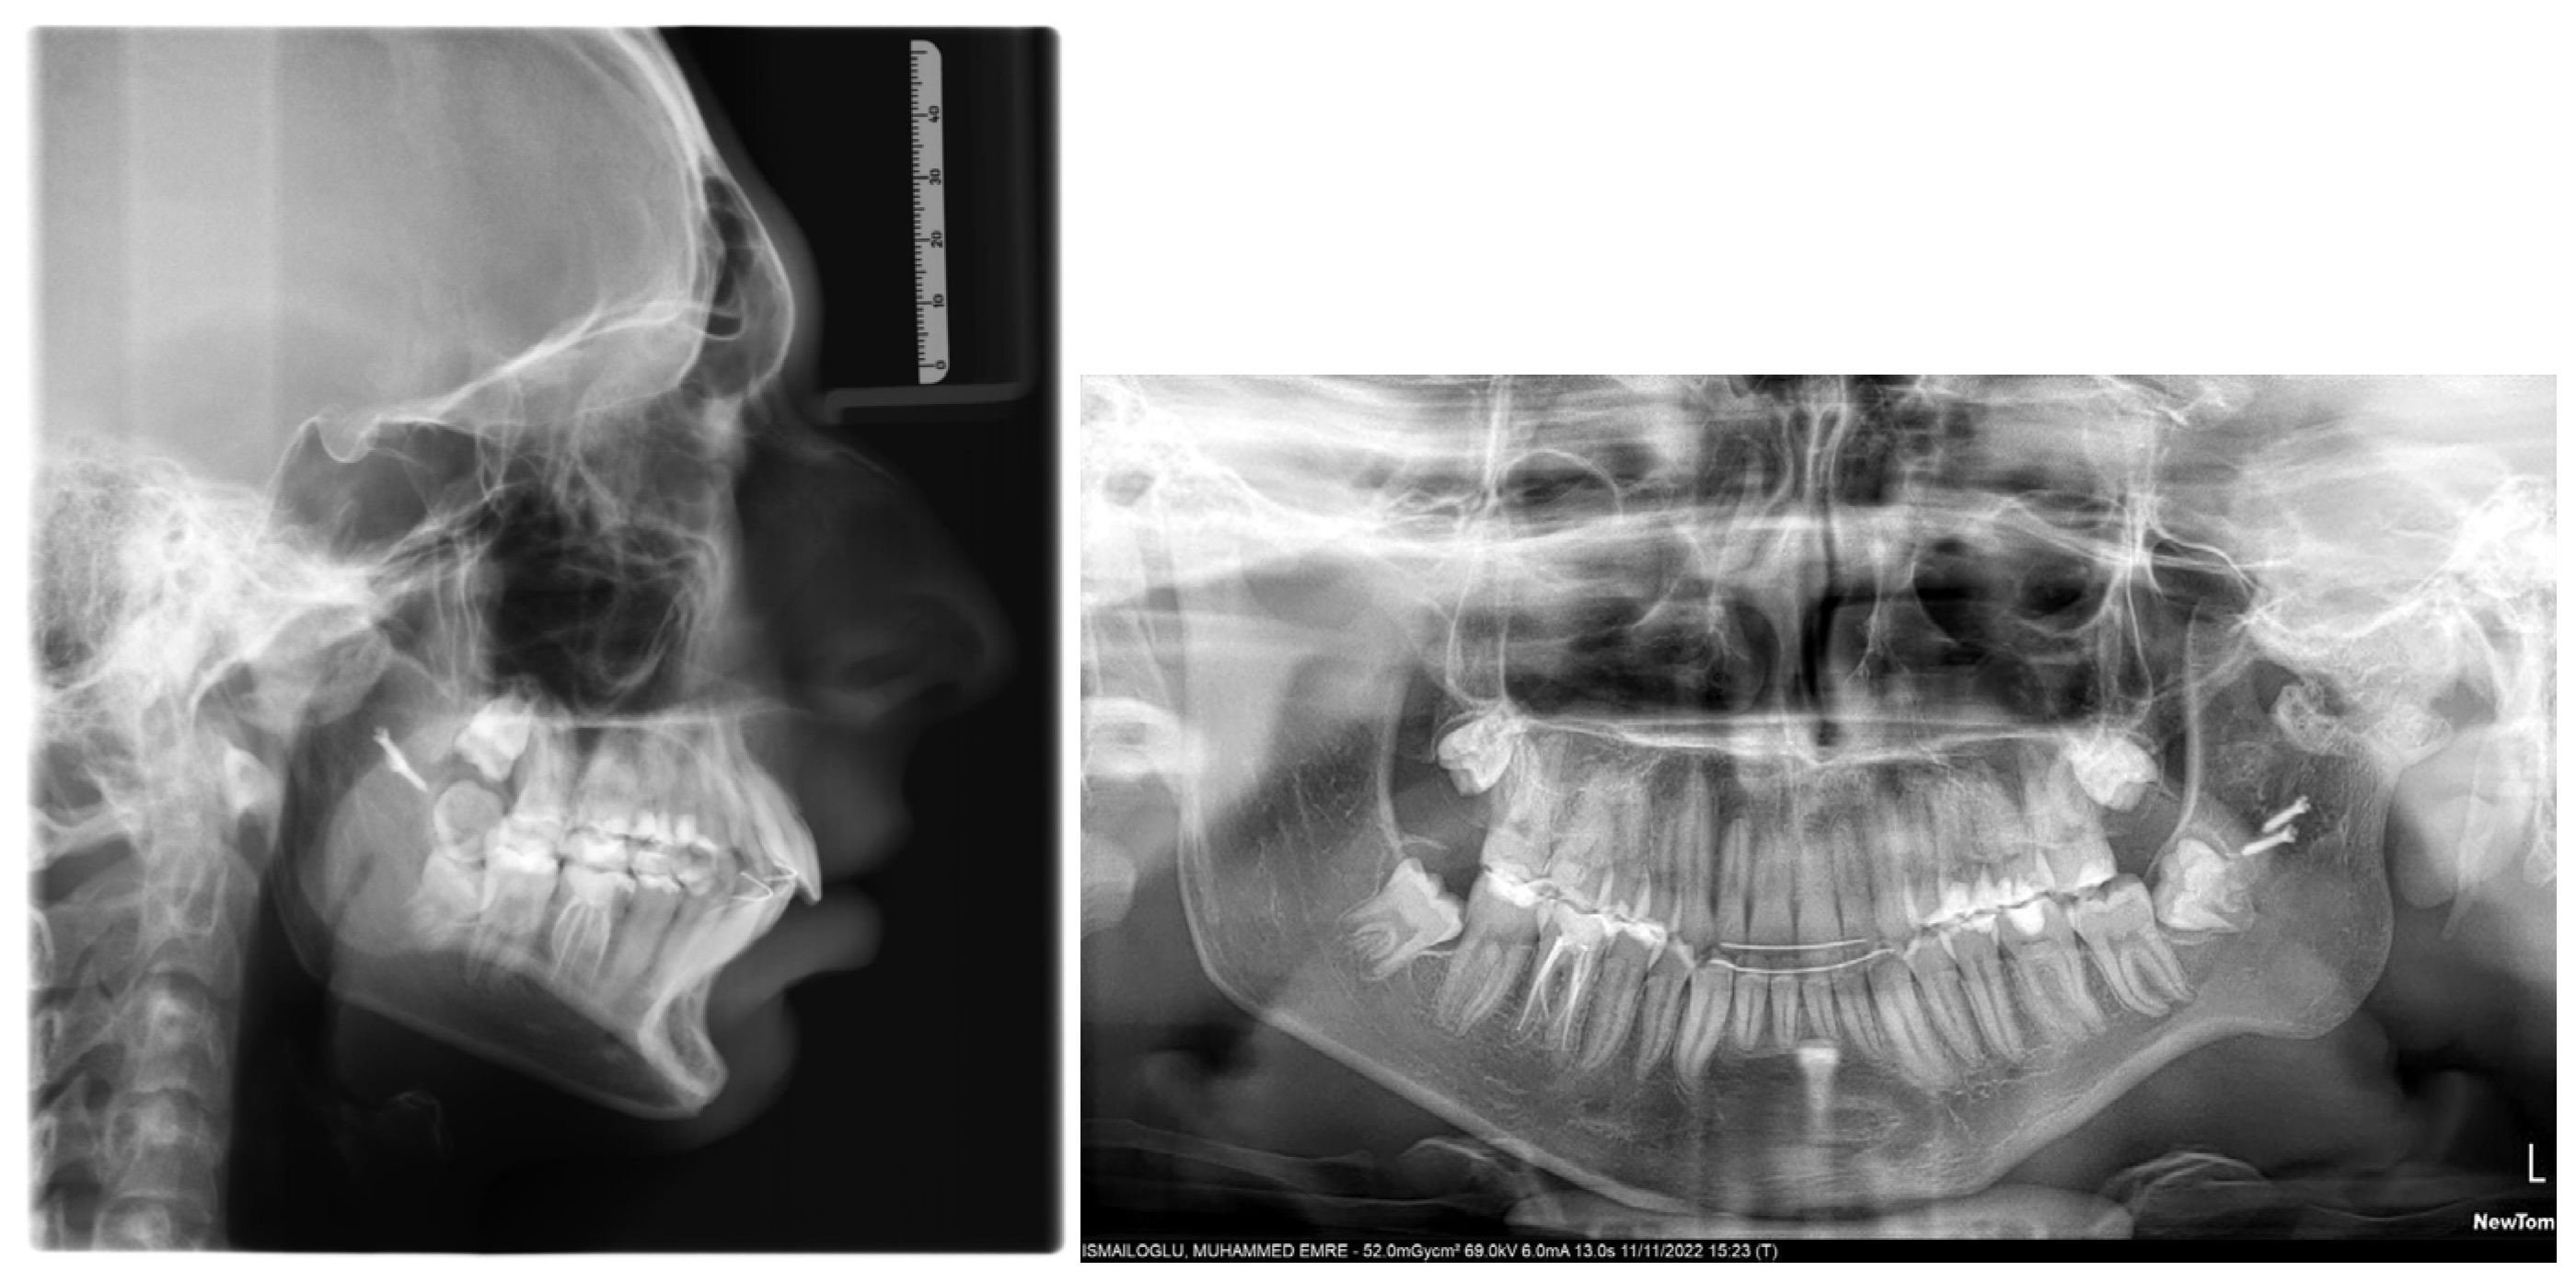

6. Treatment Results

7. Discussion